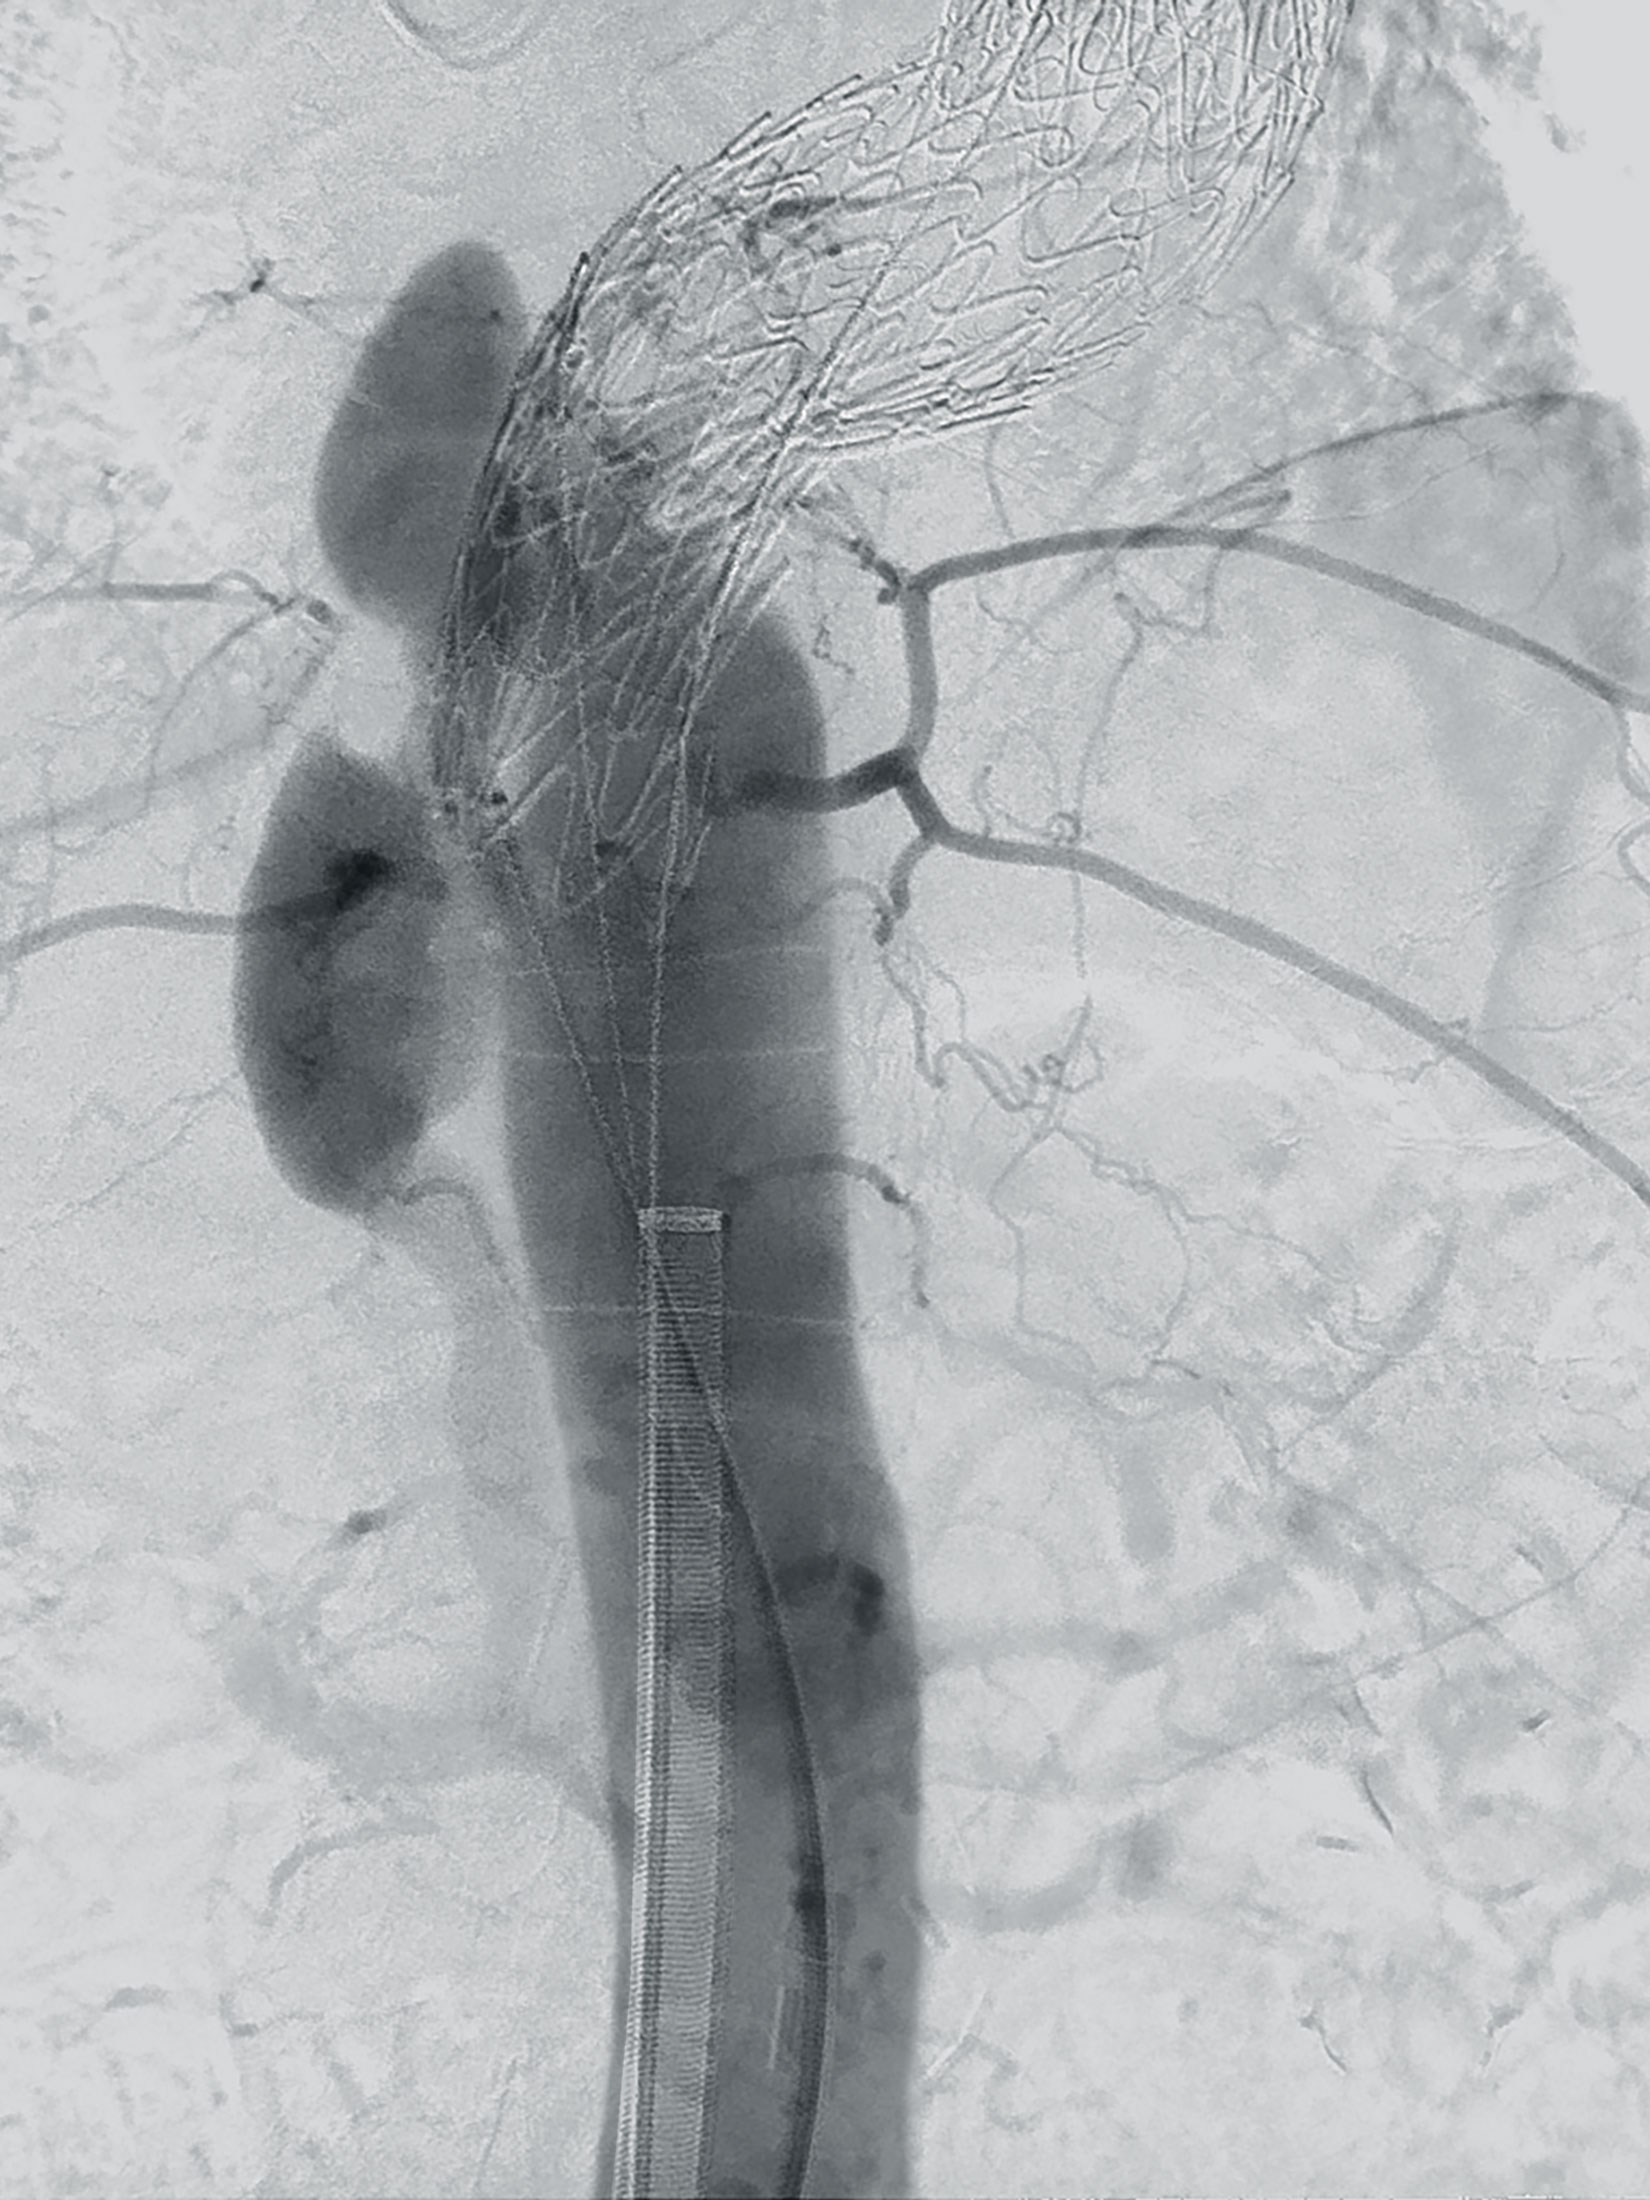

Automated 3D segmentation of the target volume

An adaptive algorithm isolates the relevant anatomical region within the image data and highlights it from the surrounding structures. Surgeons benefit from a clear visual representation of the surgical field. Vascular anomalies such as aneurysms and stenoses can be reliably identified.

Selecting the appropriate endograft

EndoSize contains a comprehensive database of all major endografts on the market. Detailed information, technical specifications, and order numbers can be accessed directly. Based on the previously determined measurements and the manufacturer’s guidelines, the user selects the optimal size of the implant. In this way, EndoSize reduces the risk of misjudgments during planning and ensures the best possible selection of implants.

Creating optimal conditions

With the help of simulated anatomical views, the ideal position of the C‑arm can be determined before the procedure. This helps to avoid parallax errors, unnecessary radiation exposure and contrast agent administration during surgery. After planning, EndoSize enables the creation of clear digital reports containing all relevant information such as measurements, selected endografts, snapshots and videos for upcoming procedures. The reports allow for early detection of potential risks and can be securely stored in the PACS system. The innovative EndoSizeMe app also allows reports to be shared with the surgical team to facilitate collaboration in complex surgical situations.